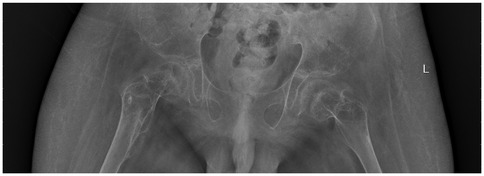

Postoperatively, the wound healed well, and the patient was discharged with instructions for continued functional rehabilitation. The patient received indomethacin (dosage calculated according to weight) after surgery to reduce the risk of recurrence. Liver and kidney function were monitored during treatment. Follow-up 6 weeks after surgery showed no new ossification, and the drug was discontinued. Follow-up at regular intervals demonstrated no recurrence (Figure 3).

Figure 3

X-ray of the pelvis showing the hip joints, sacrum, and proximal femurs. The image is labeled with an \

Figure 3. 2021.12. Eight months after surgery, no recurrence of heterotopic ossification was observed.

As of June 2024, the patient's hip joint function remained satisfactory. Due to lower body paraplegia, the patient's passive flexion range was approximately 0°–85°, extension range was approximately 0°–5°, and abduction range was approximately 0°–25°, allowing for wheelchair use. Follow-up imaging studies revealed no signs of recurrence of ossification, and the patient and family expressed satisfaction with the treatment outcome. For timeline and management decisions, please refer to Tables 1, 2.